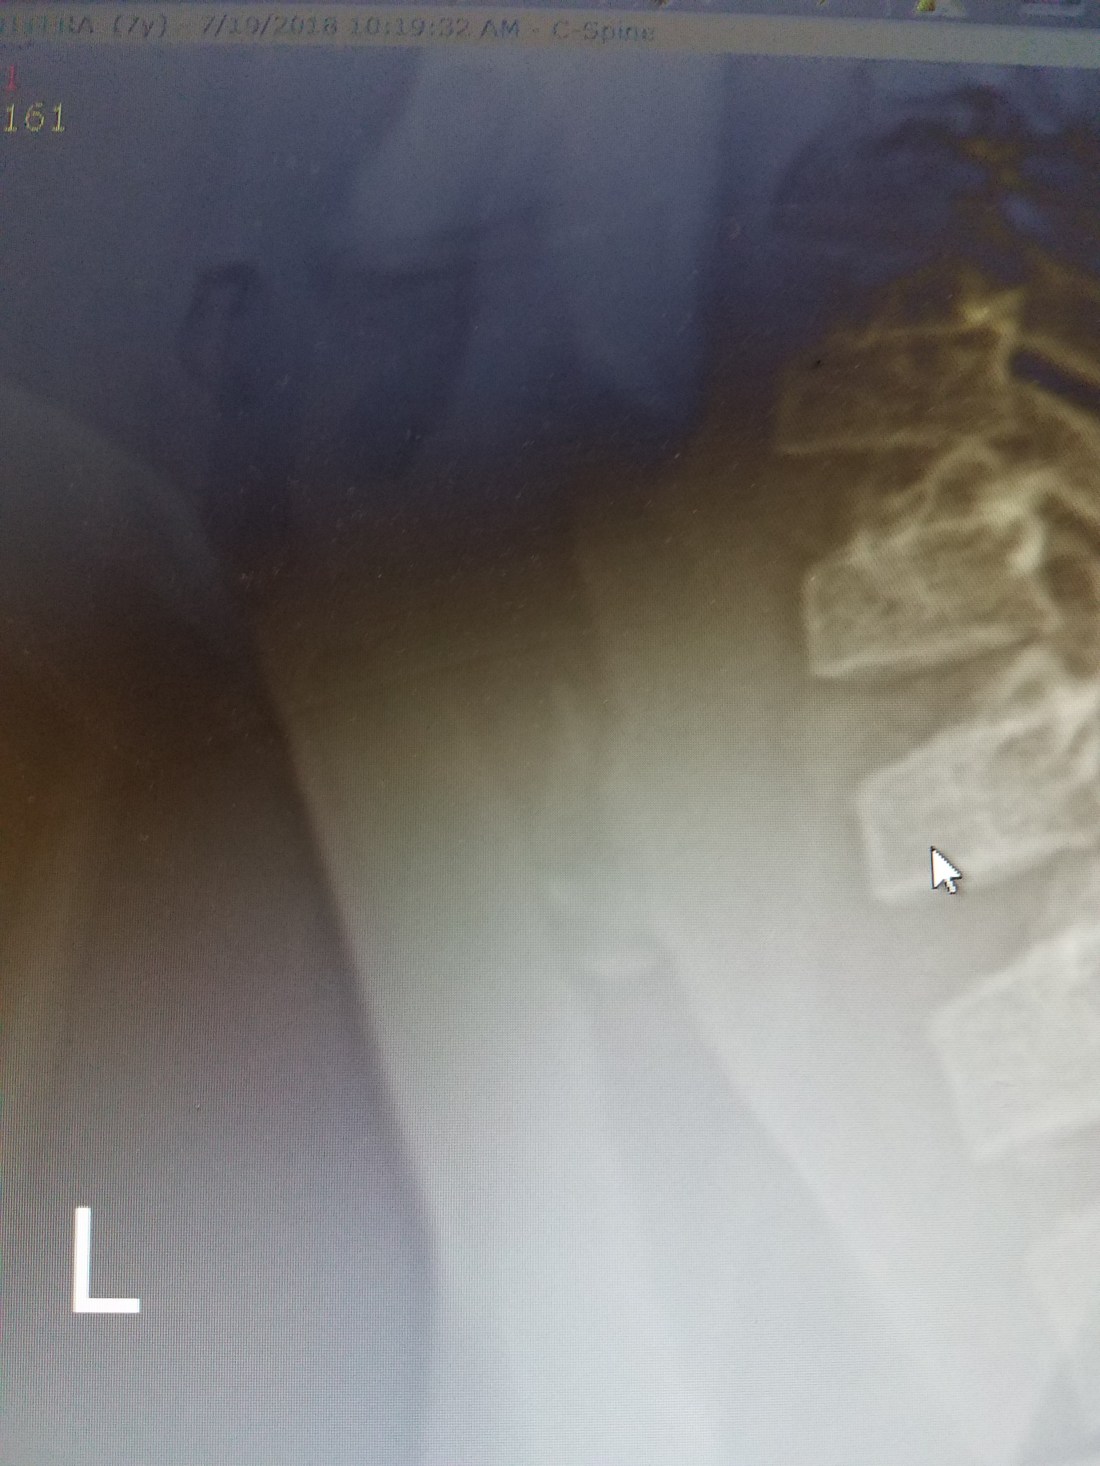

One of the children that presented to that mission was trached 5 months prior after suffering from respiratory distress one week after a traditional uvulectomy (yes, this is done all over Ethiopia in children of all ages). He caught my attention as I walked through the waiting room due to his loud inspiratory stridor. Despite his trach, he still moved air through his larynx that was accompanied by this particular type of high-pitched stridor that I have come to associate with upper airway obstruction. A lateral Xray of his neck prior to the trach and a flexible scope of the larynx was highly suggestive a something bizarre in his subglottis.